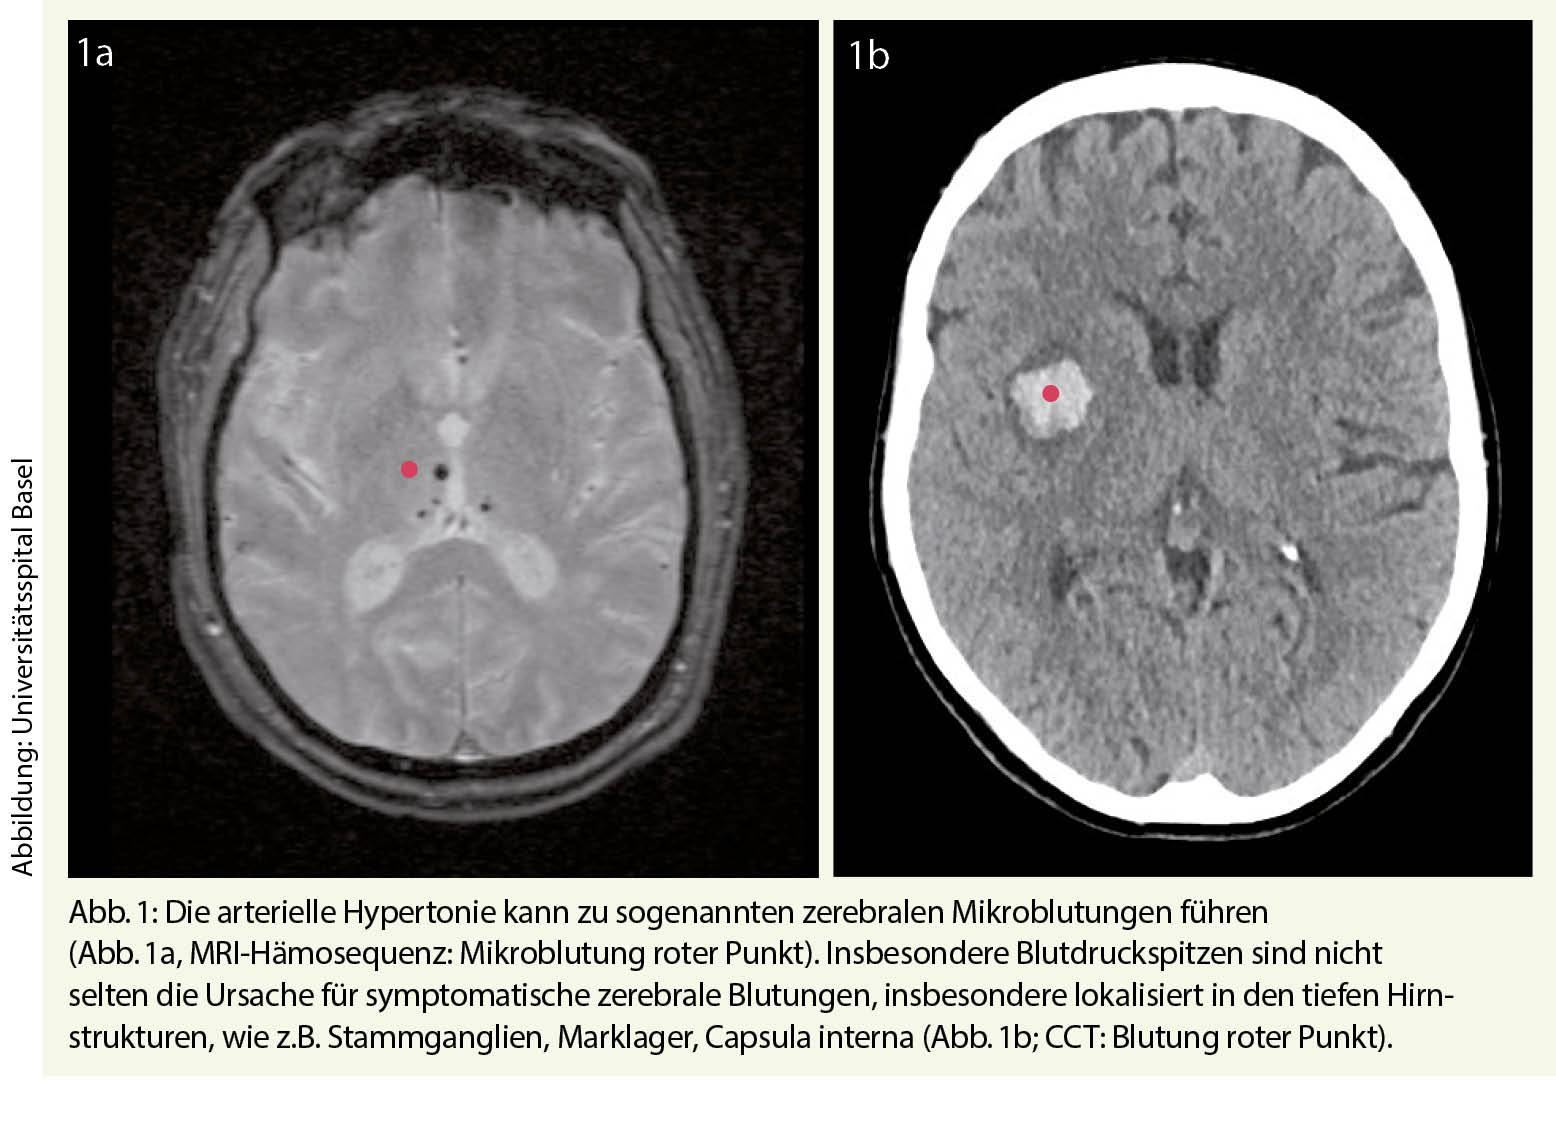

Labile Blutdruckwerte finden sich auch teilweise bei Patienten mit neurovaskulären Erkrankungen, i.e. mit einem ischämischen Hirnschlag oder einer zerebralen Blutung. Dieses ist insbesondere in der Akutphase der Fall, so dass eine vorbestehende antihypertensive Therapie ggf. angepasst werden muss. Insbesondere finden sich nicht selten erhöhte Blutdruckwerte. Dieses kann beim ischämischen Infarkt eine Reaktion auf die Minderperfusion sein. Hier sollte eine Blutdrucksenkung vorsichtig erfolgen und sich auf erhöhte Blutdruckspitzen beschränken. Bei der zerebralen Blutung – welche oftmals Folge einer arteriellen Hypertonie ist – wiederum finden sich oftmals erhöhte und labile Blutdruckwerte (Abb. 1). Blutdruckspitzen sollten vermieden werden, um einer Hämatomexpansion vorzubeugen, als Zielblutdruck wird hier ein systolischer Wert von 140 mmHg angestrebt. Langfristig kommt der Blutdruckeinstellung eine wichtige Rolle in der Sekundärprävention zu (7).